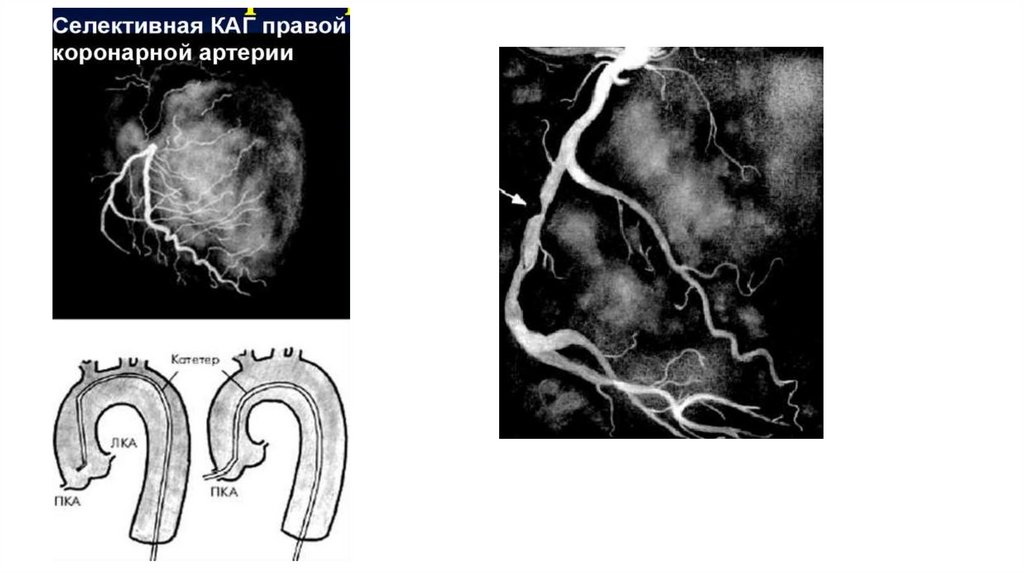

Сужение коронарной артерии атеросклеротической бляшкой (коронарография)

Контроль уровня холестерина крови

20. Сужение коронарной артерии атеросклеротической бляшкой (коронарография)